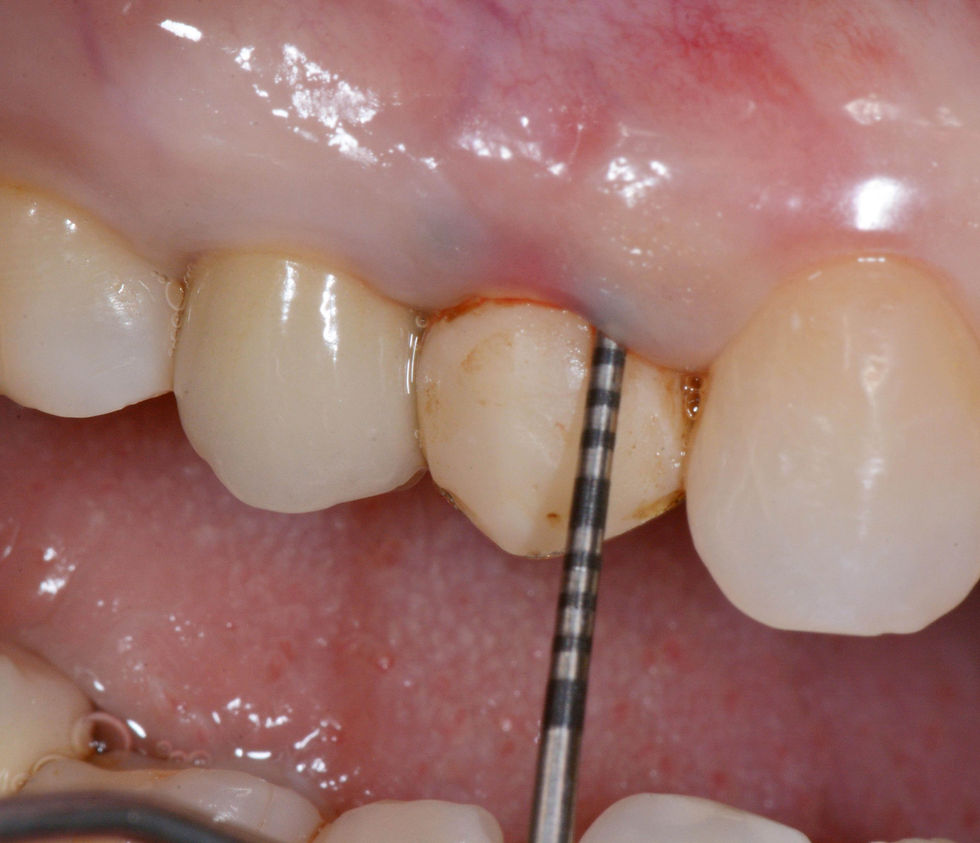

Initial situation.

Pre-operative intraoral radiograph of the element 1.4.